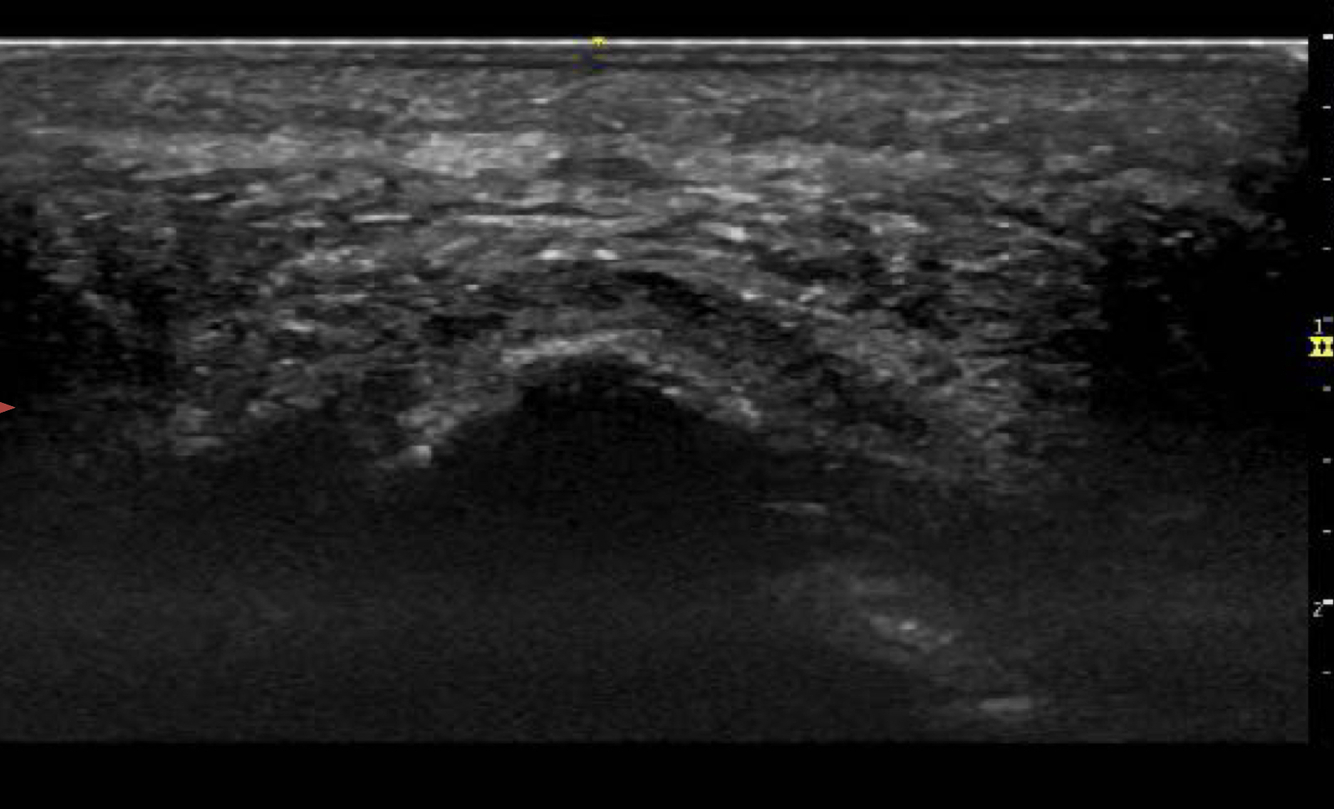

Identifier les structures suivantes

- Tibial post

- LFO

- Nerf tibial